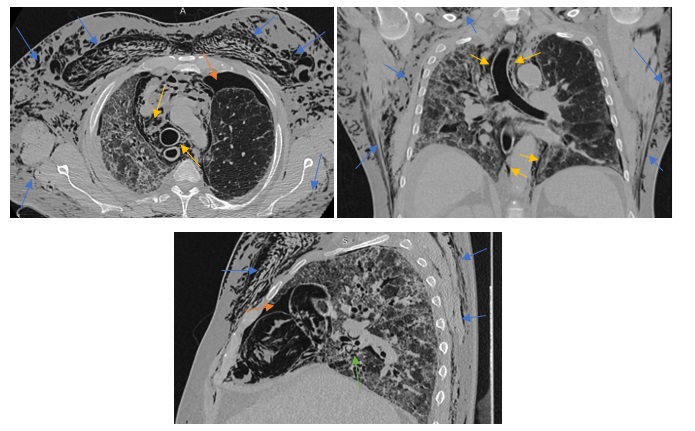

Dentro de los métodos diagnósticos, el neumomediastino se puede diagnosticar mediante radiografías o tomografía computada, donde se va a visualizar la presencia de aire (radiolucidez o hipodensidad lineales) rodeando las estructuras mediastinales. Un signo de muy alta especificidad es el llamado “signo del anillo alrededor de la arteria”, donde se visualiza una imagen radiolúcida o hipodensa en forma de anillo rodeando la arteria pulmonar, principalmente del lado derecho. Este signo ayuda a diferenciar esta entidad del neumopericardio, que puede verse similar en imágenes.

Among the diagnostic methods, pneumomediastinum can be diagnosed using X-rays or computed tomography scans, where the presence of air (linear radiolucency or hypodensity) surrounding the mediastinal structures will be visualized. A highly specific sign is the so-called “ring sign around the artery”, where a radiolucent or hypodense ring-shaped image is visualized surrounding the pulmonary artery, primarily on the right side. This sign helps differentiate this condition from pneumopericardium, which can appear similar on imaging.